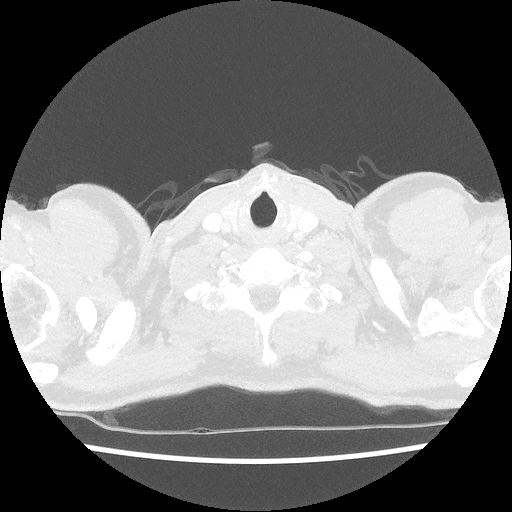

Trots als ik ben kan ik weer de binnenkant van mijn lichaam delen. Opnieuw zonder knobbels en bobbels, gewoon een super gezond lichaam van een jonge 50er.

Hierbij dus weer een mooi inzicht in mijn lichaam, ik ben er blij mee!

Zo knap dat de artsen op deze films kunnen zien of er iets mis is..

Voor mij is het een Onderwater opname

Geweldig dat dit bestaat en de artsen er raad mee weten!

Knap hoor, zeker als je te horen krijgt dat alles goed is!!